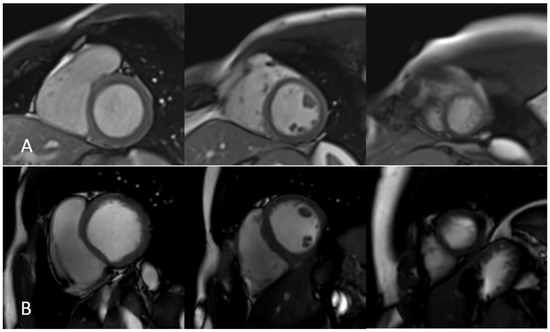

Short axis acquired using parallel imaging and compressed sensing methods. (A) string shows a functional cardiac plane acquired using parallel imaging with a 1.5T MR system, while (B) string shows an SA acquired using the CS method with a 3T MR system. SA—short axis; CS—compressed sensing.

LGE —late gadolinium enhancement sequences acquired using the compressed sensing technique. Panel (A)—Left ventricle (LV) and right ventricle (RV) short axis view at the level pf the papillary muscles; (B)—LV three chamber view; (C)—LV two chamber view; (D)—LV and RV four chamber view.